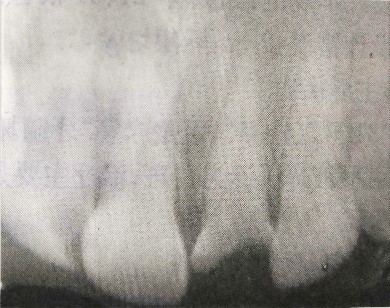

检查:21牙冠缺损,黑褐色,根管口暴露,覆盖污秽物,探诊(-),冷测(-),叩诊(+)。左上1唇侧牙龈根尖部有白色瘘管出现。X线片检查提示:21根尖区低密度影。全口牙龈红肿,探诊后出血,且下颌后牙区有附着丧失。相关情况请见下图:

(3)X线检查示21根尖部阴影。